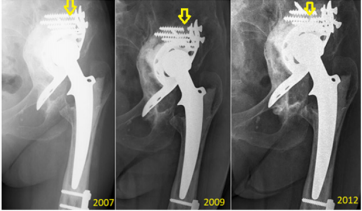

Finally, Peters et al. [5] had earlier noted poor long-term results for the BS plate in resolving pelvic discontinuity. The stability of the BS plate can be assessed by x-ray, and the imaging findings can help to predict its duration over the long-term. To this end, Gill et al. [6] showed plate instability as being indicated on x-ray by fracture of the proximal screws in the plate, together with proximal-migration of more than 5 mm, and with progression of radiolucent lines. Moreover, Van den Linde and Tonino [7] showed that fracture of the proximal screws without subsequent migration of the plate or change of inclination on x-ray does not equate to plate loosening. Our x-ray analyses agreed with these reported parameters (Figure 3). In addition, Gross et al. [8] showed that resorption of the bone grafts implanted into the pelvis upon re-implantation served as a marker of plate stability, as evidenced by x-ray imaging. This study was designed to Gross et al. [8].

Figure 3: Representative case of fracture located proximally in the BS plate but without loosening. The three x-ray images were taken over a 6-year period, as indicated. The fractured screws are indicated by yellow arrows.